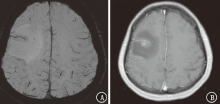

目的探讨磁敏感加权成像(SWI)在颅内转移瘤中的鉴别诊断价值。方法收集2018年 1月至2020年4月新疆维吾尔自治区人民医院住院患者中原发肿瘤为肺癌、乳腺癌、肾癌、直肠癌、膀胱癌、黑色素瘤的颅内转移瘤及胶质母细胞瘤患者63例,半定量评估肿瘤内的敏感性信号强度(ITSS)分级。比较颅内转移瘤与胶质母细胞瘤ITSS分级。结果81个颅内转移瘤中,0级为36个(44.4%),Ⅰ级为25个(30.9%),Ⅱ级为14个(17.3%),Ⅲ级为6个(7.4%);27个胶质母细胞瘤均为Ⅱ~Ⅲ级(100%)。肺癌转移瘤0~Ⅰ级占73.6%(28/38),乳腺癌转移瘤0级占84.6%(22/26),肾癌转移瘤Ⅱ级占5/6,直肠癌转移瘤0~Ⅰ级占4/5,胶质母细胞瘤Ⅲ级占77.8%(21/27)。颅内转移瘤与胶质母细胞瘤ITSS分级组间差异有统计学意义(Z=7.013,P<0.001)。采用受试者工作特征曲线分析显示,ITSS≤Ⅰ级判断颅内转移瘤的敏感性为100%,特异性为75.3%,曲线下面积为0.936(95%CI为0.891~0.980,P<0.001)。结论颅内转移瘤ITSS分级多表现为0~Ⅰ级,胶质母细胞瘤多表现为Ⅱ~Ⅲ级。SWI在颅内转移瘤中有一定的鉴别诊断价值。

ObjectiveTo explore the value of susceptibility weighted imaging (SWI) in differential diagnosis of intracranial metastatic tumors.MethodsSixty-three patients with intracranial metastatic tumors (primary tumors of lung cancer, breast cancer, kidney cancer, rectal cancer, bladder cancer and melanoma) and glioblastomas in People's Hospital of Xinjiang Uygur Autonomous Region from January 2018 to April 2020 were collected, and the intratumoral susceptibility signal intensity (ITSS) was evaluated semi-quantitatively. The grading characteristics of ITSS of metastatic tumors and glioblastomas were compared.ResultsAmong the 81 intracranial metastatic tumors, 36 (44.4%) were grade 0, 25 (30.9%) were grade Ⅰ, 14 (17.3%) were grade Ⅱ and 6 (7.4%) were grade Ⅲ. Among the 27 glioblastomas, 27 (100%) were grade Ⅱ-Ⅲ. Grade 0-Ⅰ metastatic tumors of lung cancer accounted for 73.6% (28/38). Grade 0 metastatic tumors of breast cancer accounted for 84.6% (22/26). Grade Ⅱ metastatic tumor of kidney cancer accounted for 5/6. Grade 0-Ⅰ metastatic tumors of rectal cancer accounted for 4/5. Grade Ⅲ glioblastomas accounted for 77.8% (21/27). The difference of ITSS classification between intracranial metastatic tumors and glioblastomas was statistically significant (Z=7.013,P<0.001). According to the receiver operating characteristic curve analysis, the sensitivity and specificity of ITSS ≤grade Ⅰ were 100% and 75.3% respectively, and the area under the curve was 0.936 (95%CI: 0.891-0.980,P<0.001).ConclusionThe patients with intracranial metastatic tumor usually present ITSS grade 0-Ⅰ, and the patients with glioblastoma usually present ITSS grade Ⅱ-Ⅲ. SWI has a certain value for differential diagnosis of intracranial metastatic tumors.